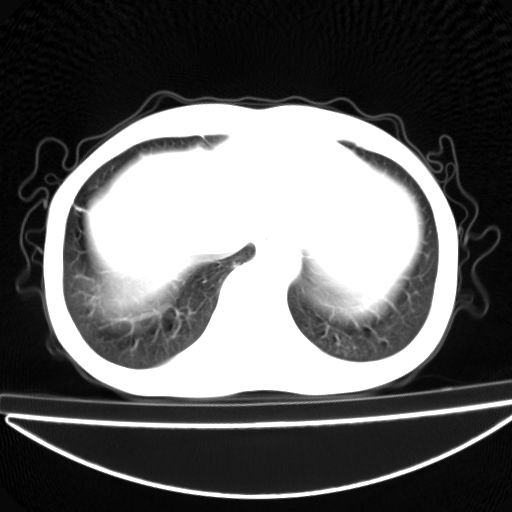

以下是引用杀毒软件在2009-4-28 17:58:00的发言:[br]考虑----左肺慢性肺脓肿形成继发上叶含气不良---抗炎后复查---待排肿瘤所致[br][br][本贴已被 杀毒软件 于 2009-4-28 18:01:26 修改过]